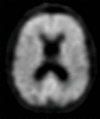

Neurodegenerative diseases are a devastating group of disorders that can be difficult to accurately diagnose. Although these disorders are difficult to manage owing to relatively limited treatment options, an early and correct diagnosis can help with managing symptoms and coping with the later stages of these disease processes. Both anatomic structural imaging and physiologic molecular imaging have evolved to a state in which these neurodegenerative processes can be identified relatively early with high accuracy. To determine the underlying disease, the radiologist should understand the different distributions and pathophysiologic processes involved. High-spatial-resolution MRI allows detection of subtle morphologic changes, as well as potential complications and alternate diagnoses, while molecular imaging allows visualization of altered function or abnormal increased or decreased concentration of disease-specific markers. These methodologies are complementary. Appropriate workup and interpretation of diagnostic studies require an integrated, multimodality, multidisciplinary approach. This article reviews the protocols and findings at MRI and nuclear medicine imaging, including with the use of flurodeoxyglucose, amyloid tracers, and dopaminergic transporter imaging (ioflupane). The pathophysiology of some of the major neurodegenerative processes and their clinical presentations are also reviewed; this information is critical to understand how these imaging modalities work, and it aids in the integration of clinical data to help synthesize a final diagnosis. Radiologists and nuclear medicine physicians aiming to include the evaluation of neurodegenerative diseases in their practice should be aware of and familiar with the multiple imaging modalities available and how using these modalities is essential in the multidisciplinary management of patients with neurodegenerative diseases.©RSNA, 2020.